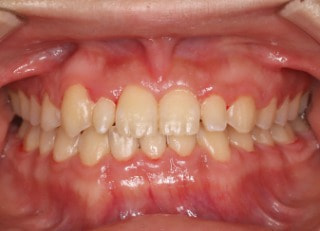

治療後(2年11ヶ月後)

解説:下顎前突上顎劣勢長傾向で、上顎両側2番が矮小歯、右下2番先天欠如症例なので、上下前歯の幅径の比率を調節する必要があるケースです。(ご本人のご都合で治療中に来院できない期間がありました)